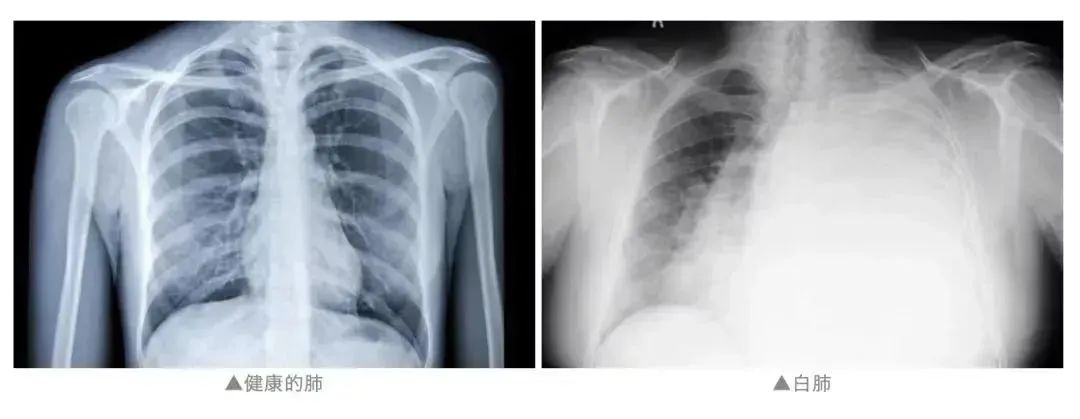

“白肺”也叫急性呼吸窘迫综合征(ARDS).健康的肺是由通气功能正常的肺泡组成,这样的肺泡充满了空气,在 X 光和 CT 上都是透光的,并且显示为「黑色」。

但如果肺部有严重的疾病,比如肺炎或者肺部肿瘤,或者有大量的积液,让健康的肺泡组织被破坏。肺里的密度增高,透光性变差,这时在 X 光和 CT 上就表现为一种烟雾笼罩的「白色」。随着肺部受到破坏的部分越来越多,白色的范围会逐渐扩大。

当白色覆盖到至少一半的肺(也有说法大致认为白色面积达到 70%~80%)时,通常就被叫做「白肺」。也就说,当「白肺」出现,可能代表着肺部问题已经比较严重了。